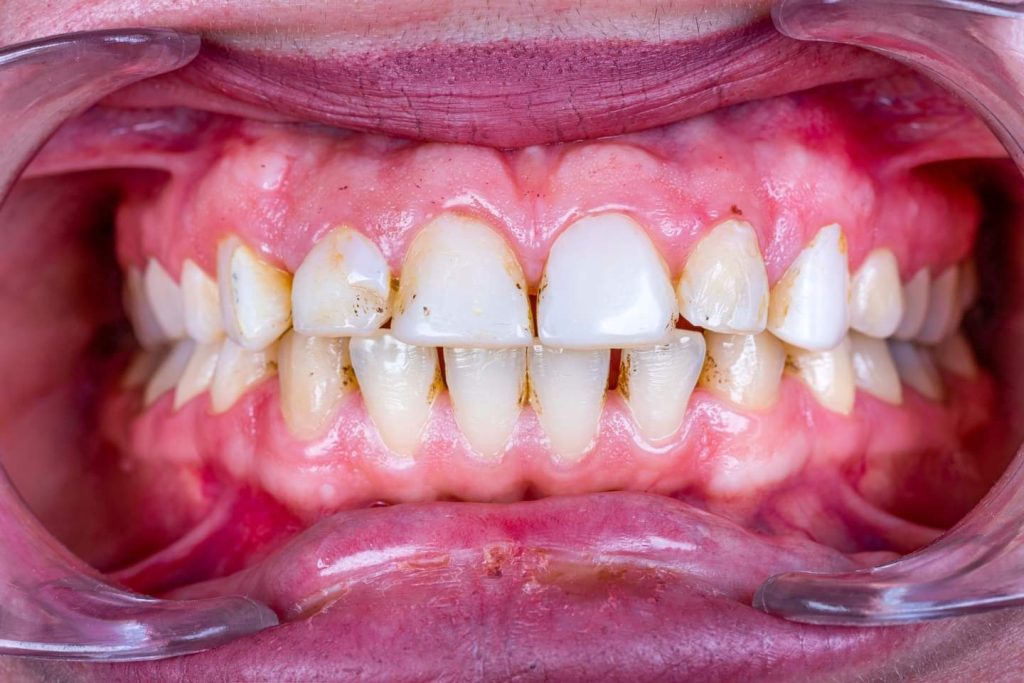

The case presented in this case report is for a 27-years-old female patient with a chief complaint of aesthetic correction for her smile. The patient was unhappy with her smile. After clinical examination, there were previous old composite veneering done poorly and incorrectly to close the multiple interdental spacing. After discussing the various treatment options (i.e., orthodontic treatment, direct, or indirect veneers), indirect ceramic veneering was selected. The step-by-step treatment protocol is presented in the images below.